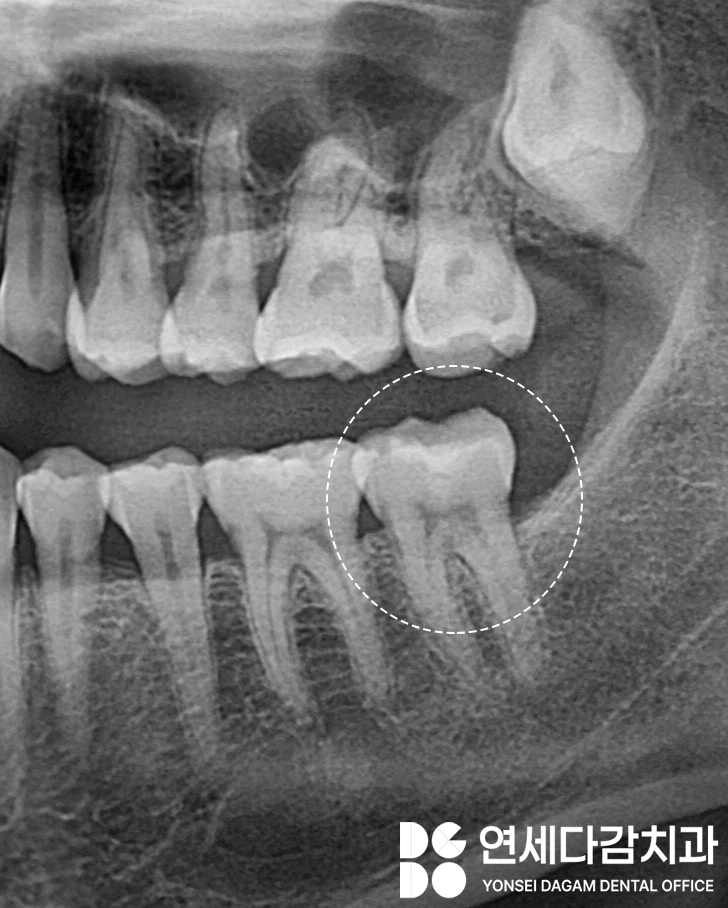

가락시장역 치과 에서는

균열의 범위를 파악하기 위해

엑스레이를 통한 정밀 관찰을 시행합니다.

가락시장역 치과 에서 표시한 것처럼

균열이 치아 내부의 신경까지

도달한 경우에는

감염이나 염증이 쉽게 발생할 수 있어

이런 경우에는 근관치료를 통해

감염원과 통증을 없애줘야 됩니다.

겉으로 미세한 균열은

엑스레이 사진으로도 구분이

어려울 때가 있는데,

간혹 치료를 위해 다듬어 봤을 때

실제로는 더 내부 깊숙이 진행되어 있는

경우도 있습니다.